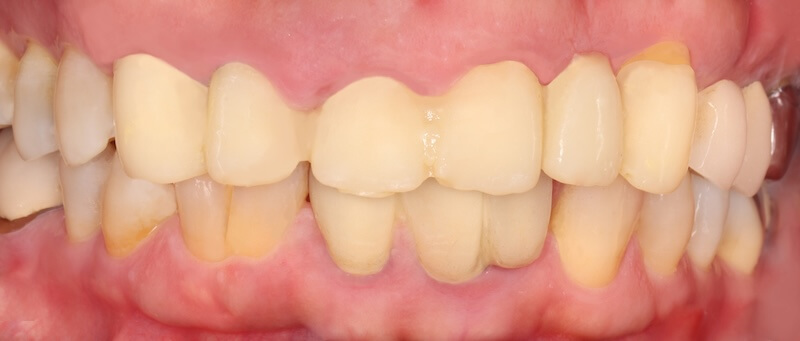

治療成果分享:重獲健康的牙齦與自然美齒

手術完成後的兩三個月左右,製作正式的假牙。最終的假牙我們設計成兩組正中門牙和犬齒相連的牙橋,和原來六顆連在ㄧ起的設計相比,清潔會相對容易很多。Ms.H 對治療前後的明顯感受是:牙齦牙周的問題獲得滿意的解決以外,新的假牙的美觀度也有大幅的改善,花時間好好投資在自己身上,非常值得。未來規律定期回診好好的維護,相信能夠常保健康穩定的治療成果。